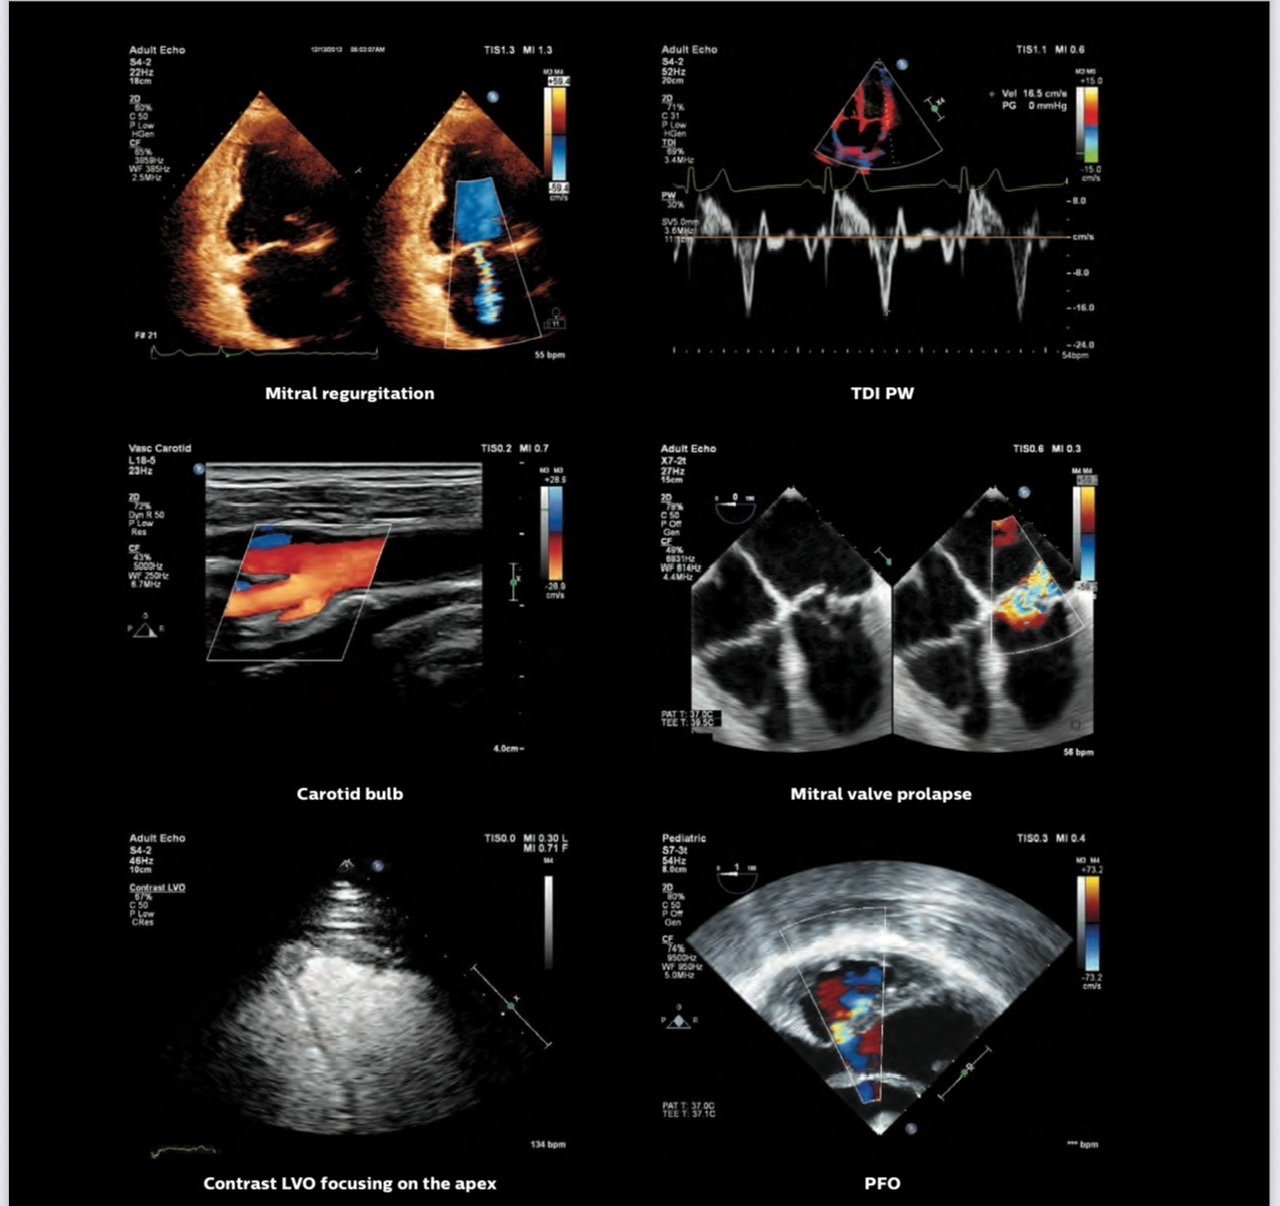

👉 Chúng tôi tự hào giới thiệu sự có mặt của Máy siêu âm tim Philips Affinity G50 phiên bản mới nhất, sản xuất tại Hoa Kỳ, vừa được trang bị tại phòng khám. Đây là thiết bị tiên tiến hàng đầu, giúp nâng cao độ chính xác trong phát hiện và theo dõi các bệnh lý tim mạch.

✅ Hình ảnh siêu nét, độ phân giải cao: Cho phép quan sát rõ ràng cấu trúc tim và mạch máu, kể cả những chi tiết nhỏ nhất.